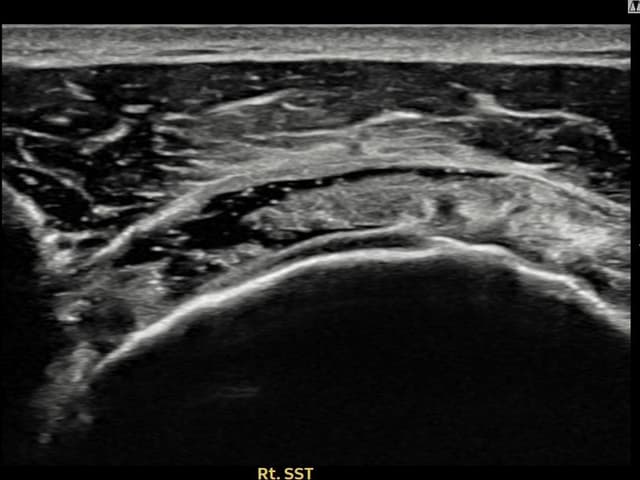

[촬영시기:23.09.01~23.11.03]

[어깨인대 축소봉합술] 우측 어깨 통증이 수개월간 지속되어 내원하셨습니다.